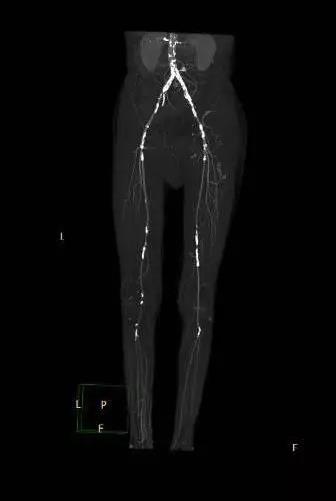

宋师傅来的时候,两个小腿都是冰凉的,看起来就像干枯的树干,细而苍白且没有多少血色。血管外科王兵教授和崔文军副主任仔细地查看了病人,考虑下肢动脉硬化闭塞症,于是立刻安排患者做了“下肢及肾动脉CTA”检查。结果如同预料的一样,患者右侧的肾动脉重度狭窄,左侧肾动脉也有明显的动脉硬化,双下肢动脉多发重度钙化狭窄、闭塞,血管如同灌了水泥一样,堵塞严重(图1)。综合患者的情况,王兵教授及崔文军副主任制定了手术治疗方案,同时处理双下肢及右侧肾动脉病变,一站式解决问题。

图1 手术前CTA,右肾动脉重度狭窄,双下肢动脉多发硬化狭窄、闭塞